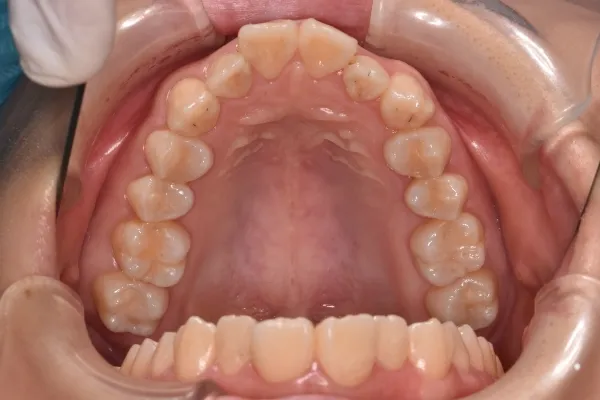

先天欠如(左右下2番)

| 診断名・主訴 | 過蓋咬合、出っ歯 |

|---|---|

| 年齢・性別 | 20歳・女性 |

| 治療期間・回数 | 2年 24回 |

| 治療に用いた主な装置 | 急速拡大 アンカー 2×4ワイヤー |

| 抜歯部位 | 左右上4番 |

| 治療費 | 70万円(税抜) |

| リスク・副作用 | 装置による違和感・疼痛・歯肉退縮・歯根吸収・虫歯のリスクなど |